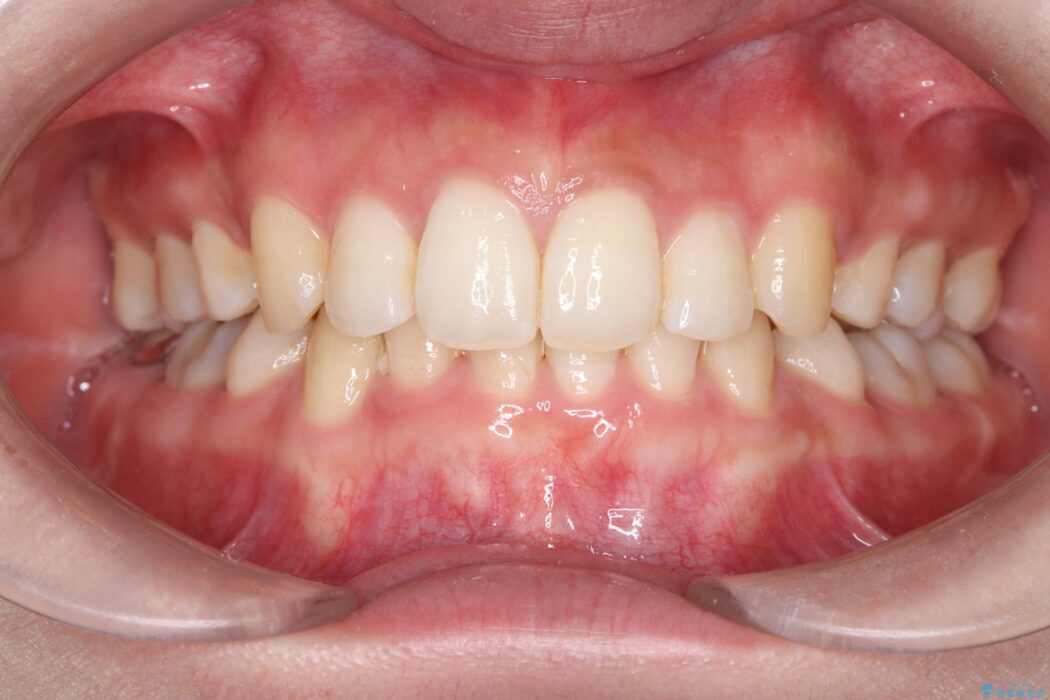

治療後について

長年の悩みだった重度の乱れが解消され、口元の突出感もすっきり改善。見た目も機能も安定した、理想的な歯並びを獲得していただけました。